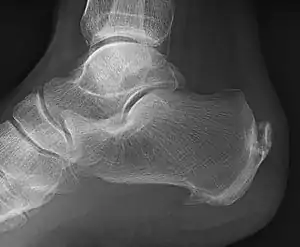

A calcaneal spur (also known as a heel spur) is a bony outgrowth from the calcaneal tuberosity (heel bone).[1] Calcaneal spurs are typically detected by x-ray examination.[2] It is a form of exostosis.

| A radiograph showing osteophytes on the posterior and inferior aspects of the calcaneus | |

An inferior calcaneal spur is located on the inferior aspect of the calcaneus and is typically a response to plantar fasciitis over a period, but may also be associated with ankylosing spondylitis (typically in children). A posterior calcaneal spur develops on the back of the heel at the insertion of the Achilles tendon.[3]

An inferior calcaneal spur consists of a calcification of the calcaneus, which lies superior to the plantar fascia at the insertion of the plantar fascia. A posterior calcaneal spur is often large and palpable through the skin and may need to be removed as part of the treatment of insertional Achilles tendonitis.[3]